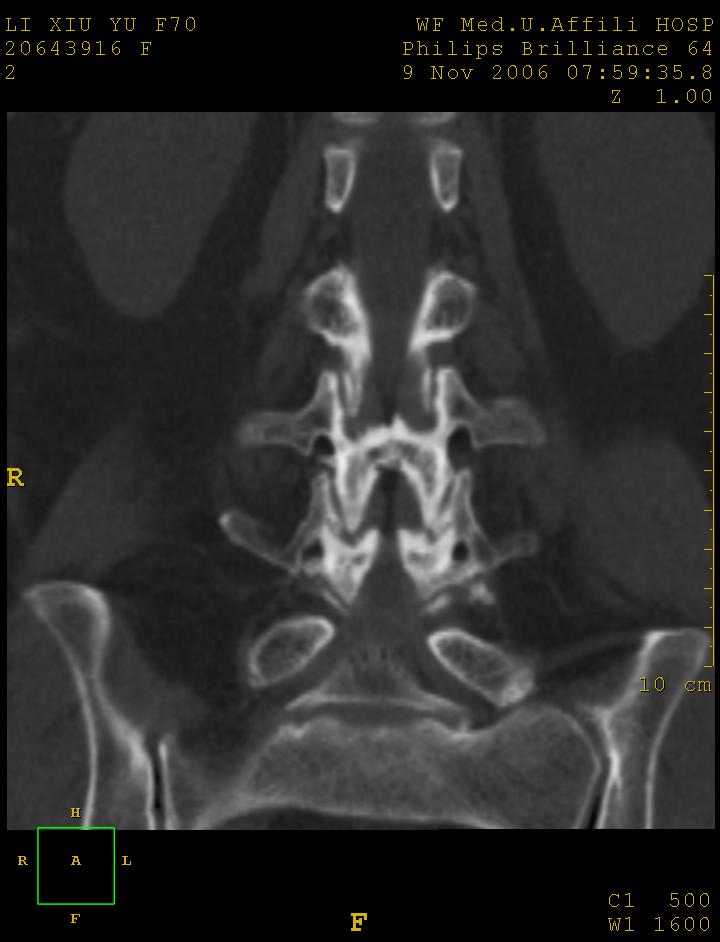

女,70岁,腰痛

1、腰4椎体1度滑脱。2、腰椎及椎小关节退行性骨关节病。3、腰3-骶1椎间盘病变。

1 腰4椎弓崩裂,腰4椎体向前ι度滑脱并椎小关节交锁,腰4/5小关节明显增生硬化,间隙内可见真空征。

2 腰椎间盘不同程度膨出,腰4/5、腰5/骶1椎间盘突出,腰4/5椎间隙变窄,腰5/骶1间盘变性(间隙内可见真空征)。

诊断:腰椎退行性骨关节病。